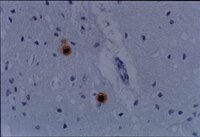

Prion diseases or transmissible spongiform encephalopathies are a group of fatal neurodegenerative diseases caused by an abnormal form of prion protein (PrP(sc)). In this study, we developed a sensitive histochemical detection of PrP(sc) deposits in a Gertsmann-Sträussler-Scheinker disease (GSS) patient using toluidine blue-O staining, a specific reagent to stain mucins and mucopolysaccharides. Detection of prion deposits correlated with immunohistochemistry using anti-prion antibodies. Control assays were performed using amyloid-beta (Abeta) plaques from Alzheimer's disease (AD) brains. Our results demonstrated that toluidine blue-O staining allowed to recognize 69.1+/-2.6% of the total plaques recognized by the anti-prion antibody. Furthermore, in the 15 studied brain regions from the GSS patient, toluidine blue-O revealed the same recognition pattern as anti-prion labeling. Toluidine blue-O stained specifically the prion deposits but not the Abeta plaques in AD brains. The specificity of the technique was confirmed in a Creutzfeldt-Jakob disease brain. This method opens several possibilities for postmortem diagnoses. Our results also suggest the relevance of specific post-translational modifications of PrP(sc), identified by toluidine blue-O, that might participate in the transformation of PrP(c) to PrP(sc). | 11810193